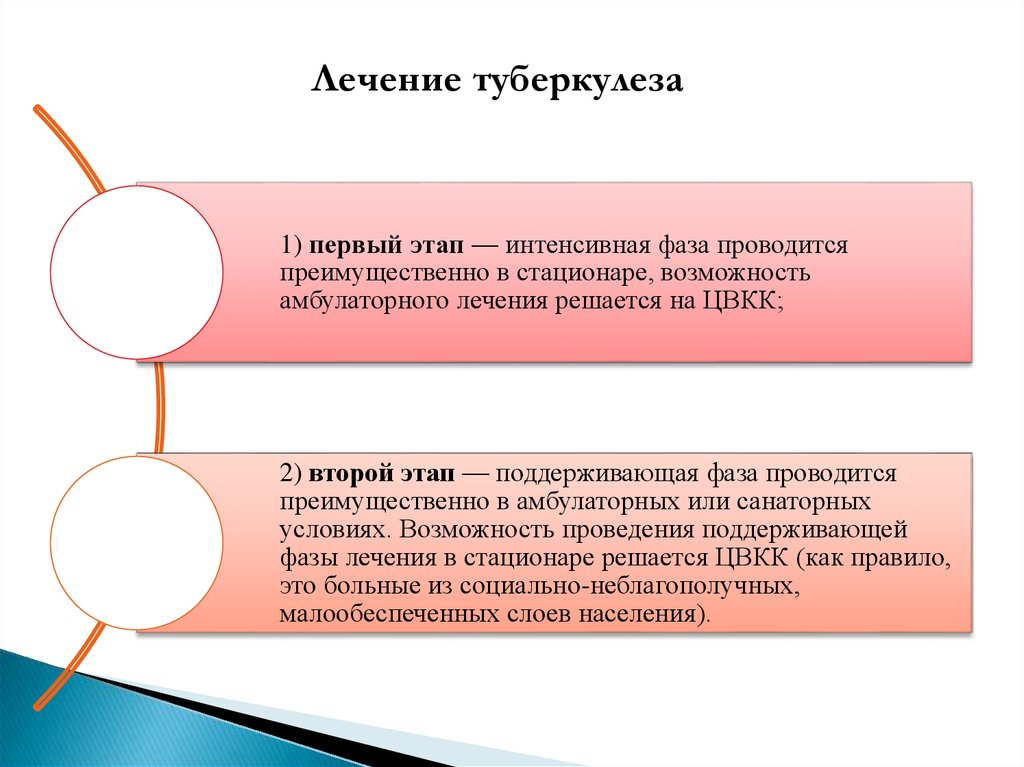

Лечение туберкулеза: Методики химиотерапии

Раздел: Визуальный дайджест